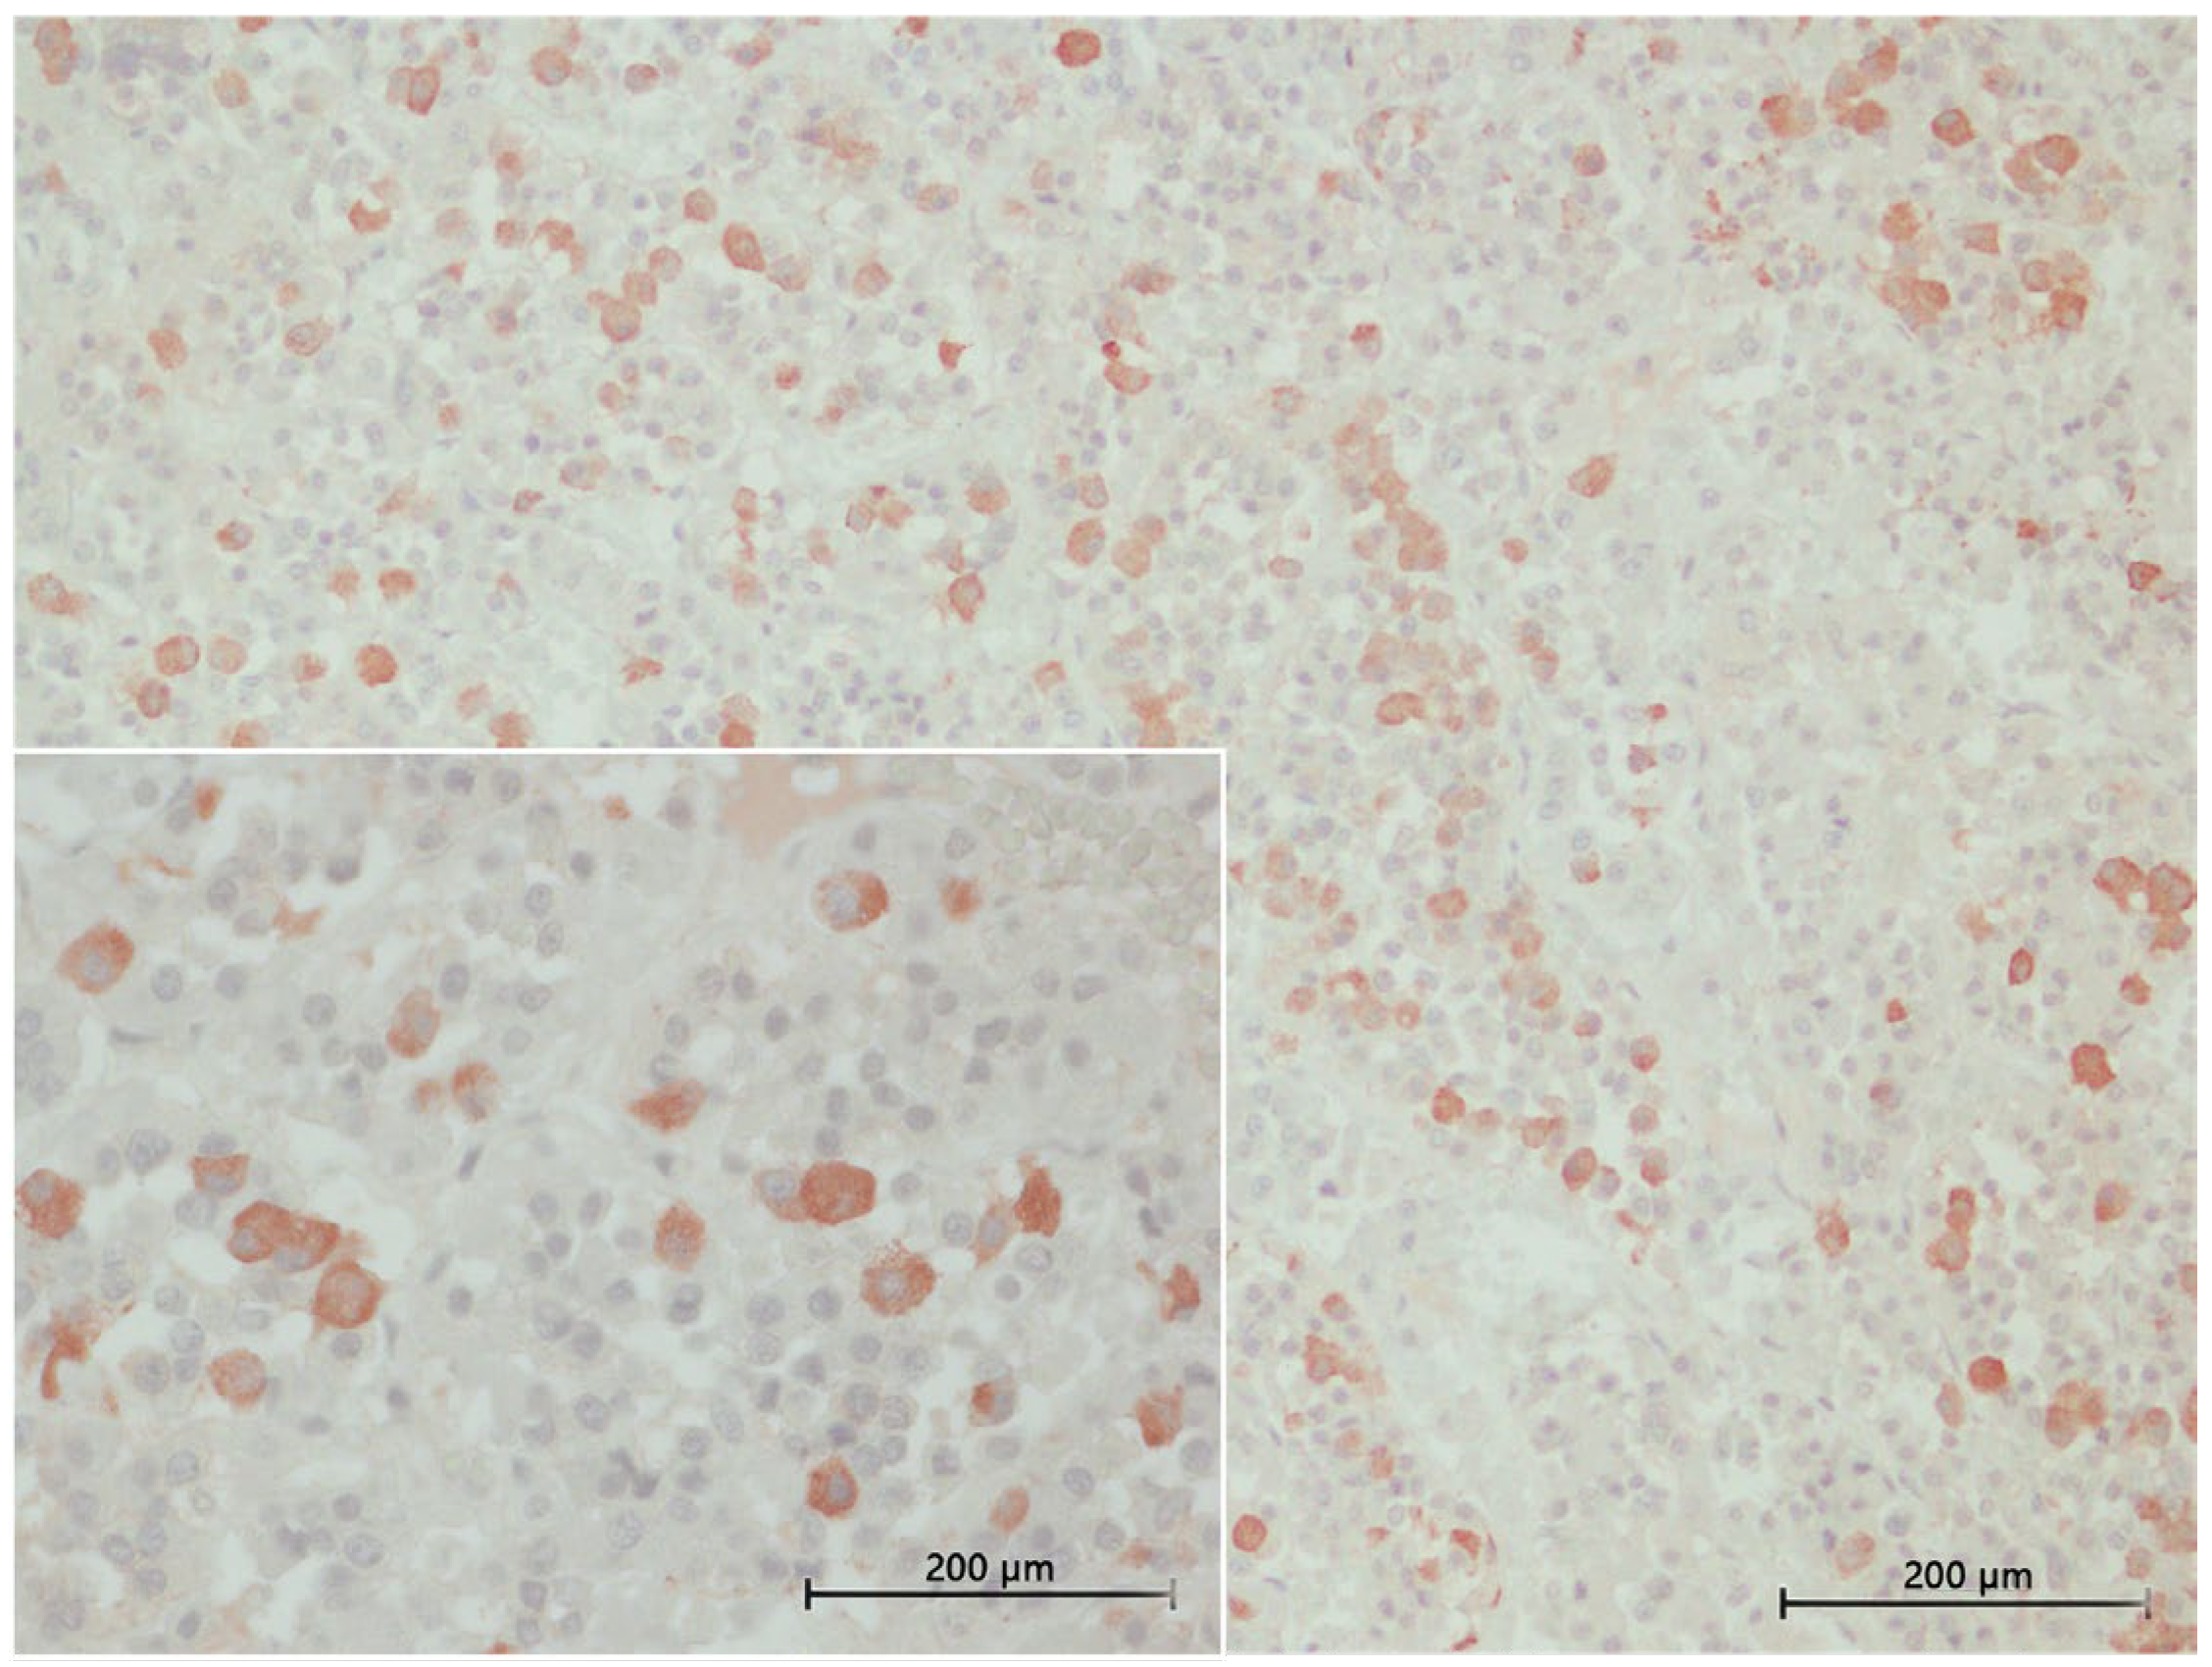

3.4. Inmunohistochemical Study

3.4.1. ACTH Labelling

3.4.2. MSH Labelling